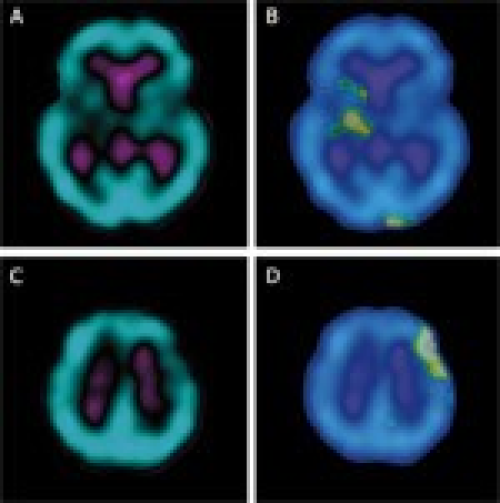

Usefulness of 99mTc-ECD brain SPECT with voxel-based analysis in evaluation of perfusion changes early after carotid endarterectomy

Anna Nocuń, Marek Wilczyński

DOI: 10.12659/MSM.881771

Med Sci Monit 2011; 17(5): CR297-303

Anna Nocuń, Marek Wilczyński, Jacek Wroński, Beata Chrapko